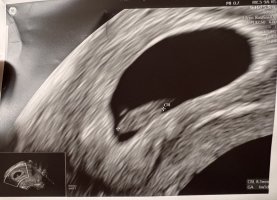

13mm og tilbake igjen til 8+2hematomet kan ses under og mot høyre av fostersekken, og har endret seg veldig, så dette ser lovende ut